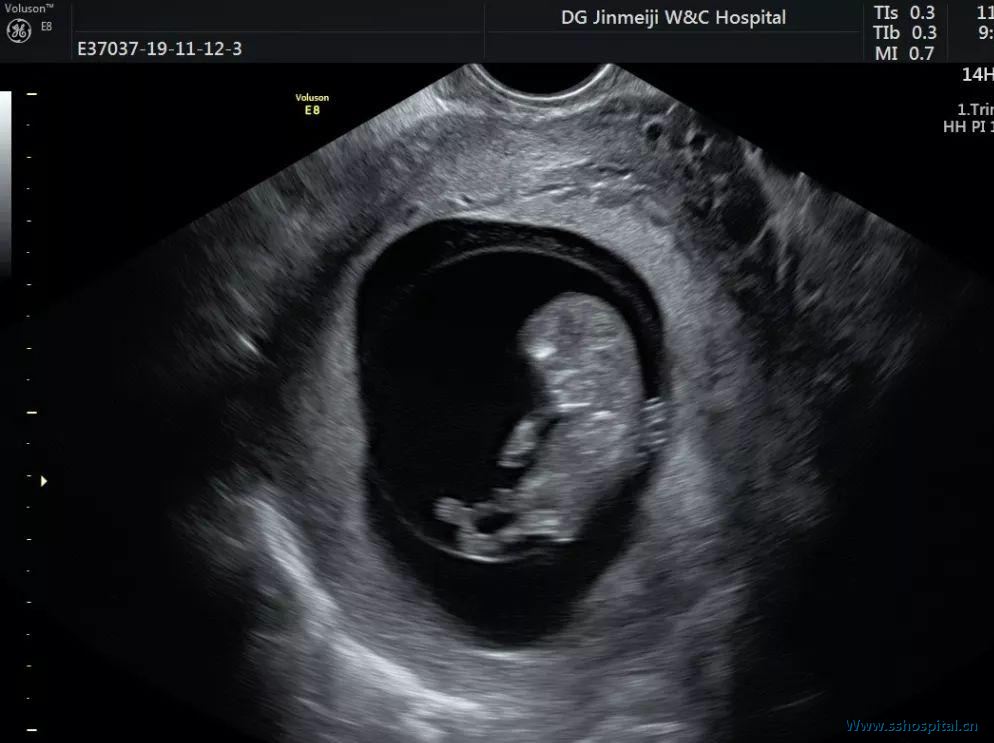

临床将患者收入住院,立即给予导尿,约 900 ml,并留置导尿管。常规实验室检查未见异常。临床医师采用手法复位(排空患者膀胱,取膀胱截石位,医师一手的两手指置于******后穹窿向上推子宫底,另一手放于腹部逐步探及宫底,两手一起复位),后复查超声,发现子宫、宫颈和宫内孕囊均恢复正常形状(图 3 和图 4)。

图 3 经手法复位后,子宫、宫颈恢复正常形状

图 4 解除箝闭后的胎儿